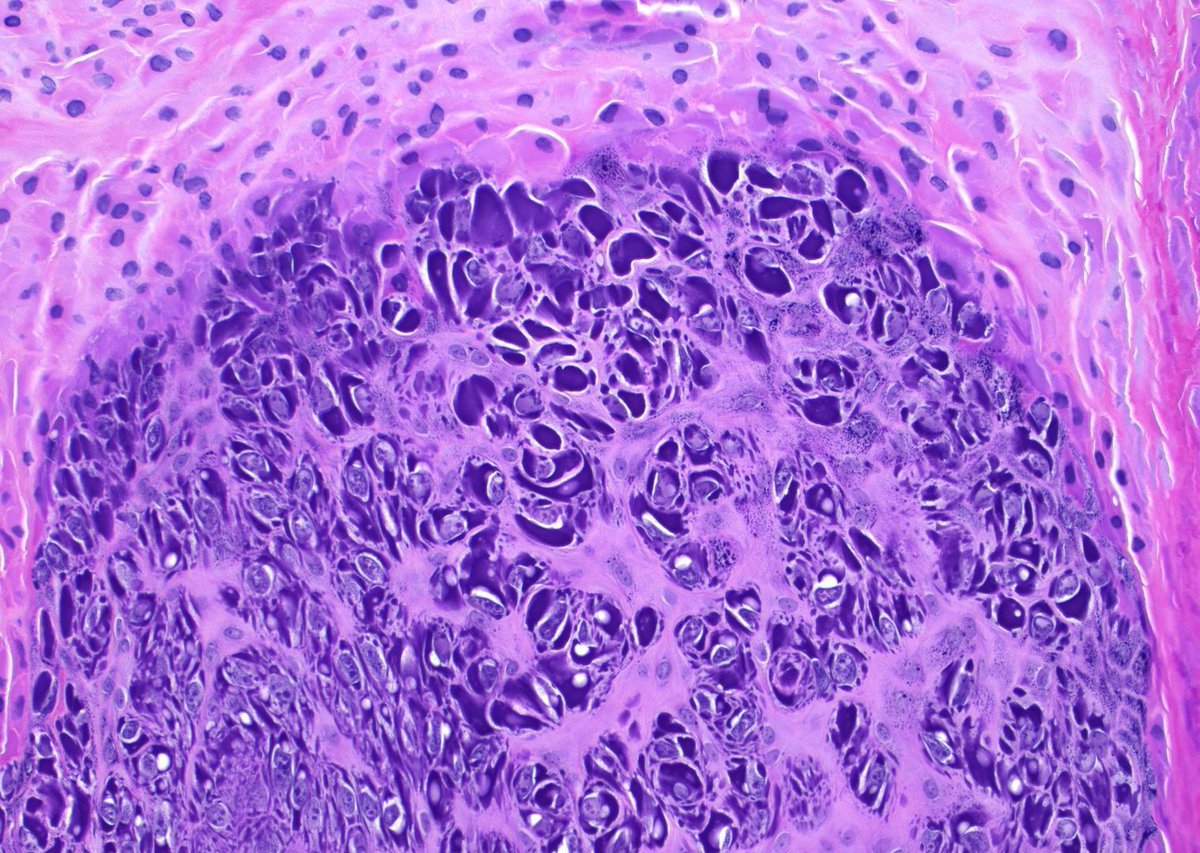

Classic pattern in pathology (with a fun name!). What is this called? What tumors have it? Answer & more pics: kikoxp.com/posts/15107 Video: kikoxp.com/posts/15033 #BSTpath #pathologists #pathology #pathTwitter #ENTpath #GUpath #USMLE

Classic pattern in pathology (with a fun name!). What is this called? What tumors have it?

Answer & more pics: kikoxp.com/posts/15107

Video: kikoxp.com/posts/15033

#BSTpath #pathologists #pathology #pathTwitter #ENTpath #GUpath #USMLE